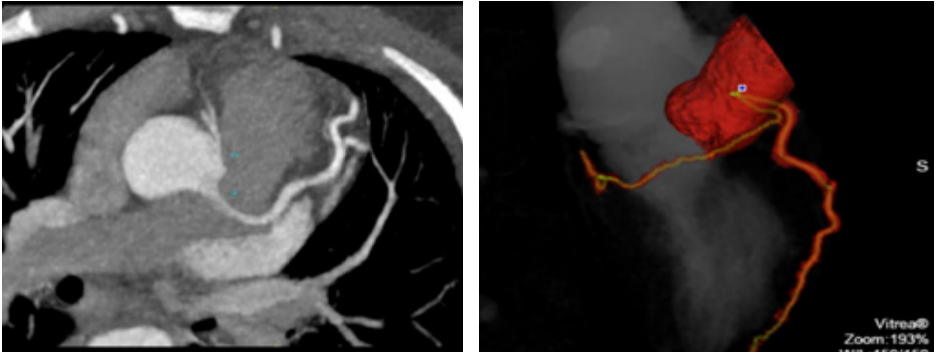

A 32 years young woman with history of hypertension, dyslipidaemia and active smoking, presented to the Emergency Department of our hospital with symptoms of unstable angina pectoris. The patient was a diagnosed case of Mid-Aortic-Syndrome with bilateral renal artery stenosis (2000) and underwent resection of the stenotic intermesenterial aortic segment with implantation of PTFE-Prosthesis and bilateral implantation of renal arteries at the very young age of 12 years. Her physical examination was unremarkable with no evidence of dyspnoea, lung congestion, murmurs or signs of raised jugular venous pulse (JVP). Her heart rate was 76 bpm and the blood pressure was stable at 130/80 mm Hg. Her daily medication was Aspirin 100 mg, Candesartan 32mg, Bisoprolol 7.5mg and Atorvastatin 40mg. An electrocardiogram (Figure 1) on admission demonstrated sinus rhythm with early repolarisation changes and laboratory analysis revealed normal blood count with normal liver and kidney functions. Initially, the cardiac biomarker (Troponin T) was 34pg/ml (normal range < 14 pg/ml) but follow up results showed a significant rise from 34pg/mL to 661 pg/mL. With the diagnosis of an acute myocardial infarction on the basis of a sudden exponential change in the Troponin levels, the patient underwent coronary angiography through the right femoral artery route (Figure 2), which revealed a disease free left main coronary artery. We were unable to identify the RCA ostium, for which an Aortography was performed and it revealed the RCA originating from left coronary sinus. Further confirmation of the anomality was done through a coronary computed tomography angiography (Figure 3). The coronary computed tomography angiography (CCTA) showed the anomalous origin of a hypoplastic RCA from left coronary sinus ventral to the left main origin, lying between the aorta and the pulmonary trunk with a negative Agatston score. The transthoracic echocardiogram revealed a normal left ventricular function without any regional wall motion abnormalities, diastolic dysfunction Grade II and minimal mitral- and tricuspid-regurgitation. Laboratory investigation for cardiotropic virus marker revealed increased values of IgG-EBV, which most probably reflects an old Epstein-Barr virus (EBV) Infection.

Figure 3 Coronary CT Angiography.

The diagnosis of ACAOS is usually incidental as most patients are asymptomatic. The symptomatic patients present to the emergency usually with exertional syncope, angina, or palpitations.15 Imaging through a coronary computed tomography angiography (CCTA) is very helpful and effective in diagnosing ACAOS and excluding other coronary anomalies with high accuracy,16 as well as being an accurate technique for distinguishing patients at high risk for adverse events.17 In imaging studies yit was demonstrated that the increased risk for MACEs was dependent on specific CT-derived anatomical criteria.17